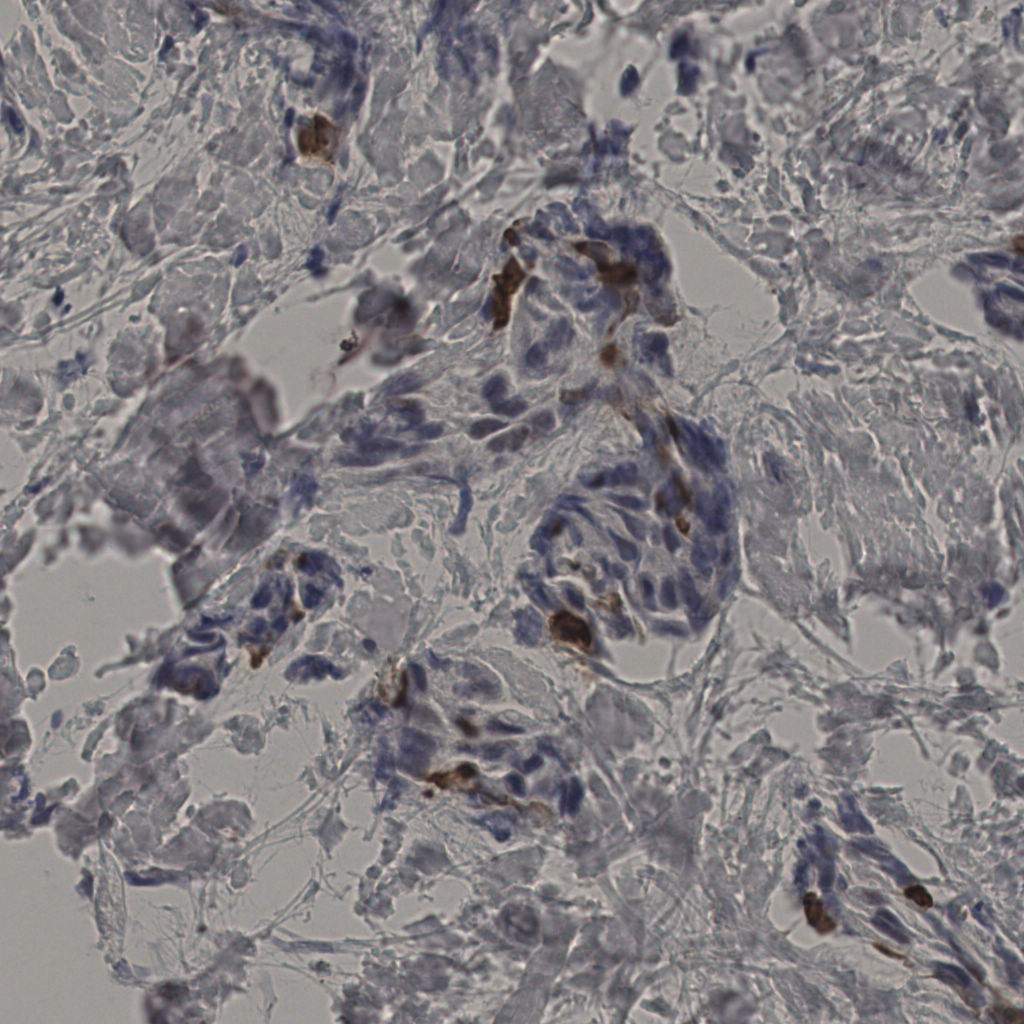

5.31%

Ki67 指数

阴 19502

阳 1093

切片统计

总切片

2970

有效

554

已标记

有效率

19%

标记后

标记前